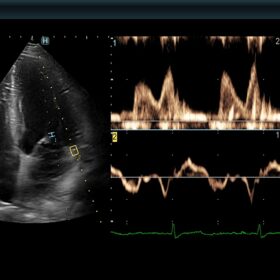

Ultrasound ARIETTA 850 SE – Image Gallery and Videos

Cardio 2D and Color mode